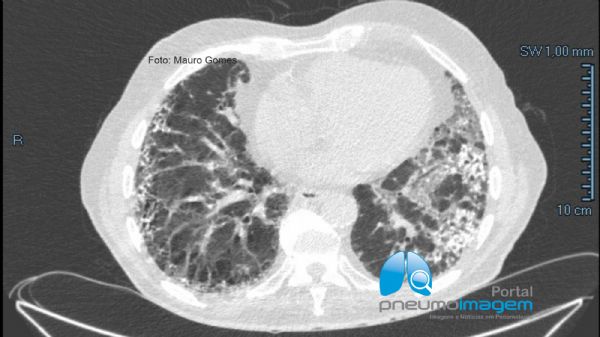

Nos cortes com a janela para o mediastino é possível se observar melhor os focos de calcificação intersticial.

In CT slices with the window to the mediastinum, it is possible to better observe the foci of interstitial calcification.